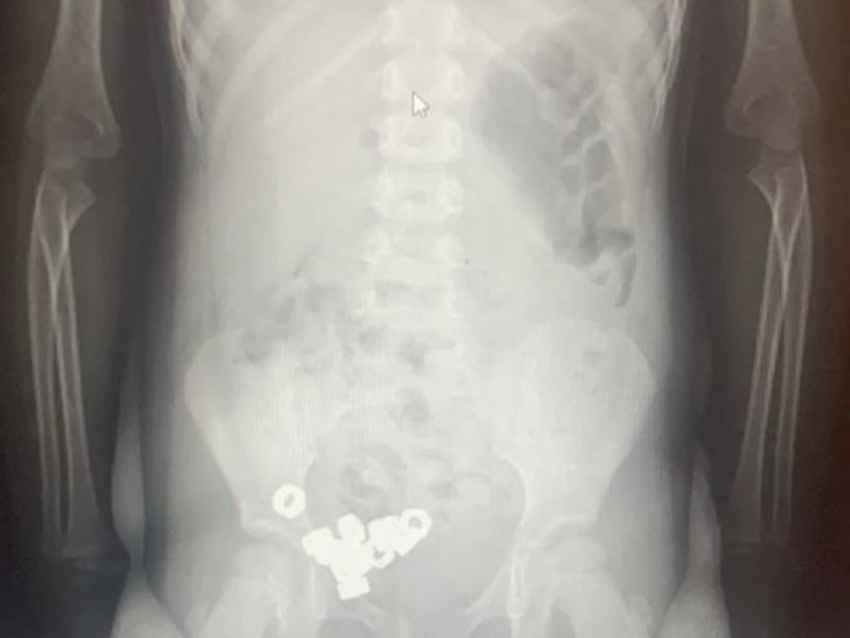

16 гаек проглотил трехлетний ребенок в Воронеже

Симптомов у маленького пациента не было, но рентген показал 16 маленьких гаек в желудочно-кишечном тракте. Из-за высокого риска осложнений ребенка госпитализировали, чтобы наблюдать за его состоянием.

«Учитывая, что инородные тела были не инертные и не магнитные, врачи выбрали консервативную тактику: назначили диету, покой, контроль стула и рентгенографию в динамике», – сообщили в министерстве здравоохранения Воронежской области.

К третьему дню гайки вышли естественным путем. Маленький пациент уже выписан из больницы.